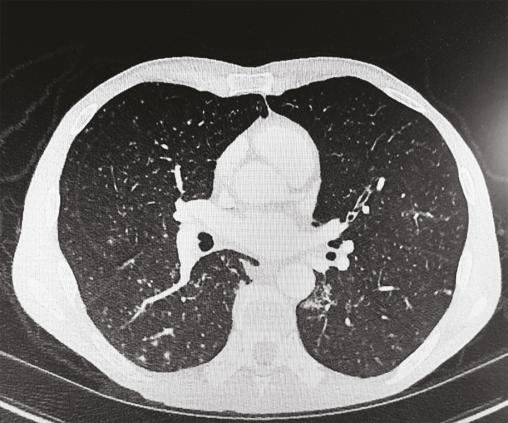

Cet homme de 56 ans vivant avec le VIH et en rupture thérapeutique, était adressé pour une gingivite ulcéro-nécrotique (fig. 1) et des adénopathies sous-mandibulaires bilatérales, évoluant depuis trois semaines. La biopsie a objectivé des granulomes épithélioïdes gigantocellulaires, une nécrose caséeuse (fig 2) et des mycobactéries. L’imagerie thoracique a révélé des nodules pulmonaires évoquant une miliaire tuberculeuse (fig 3).